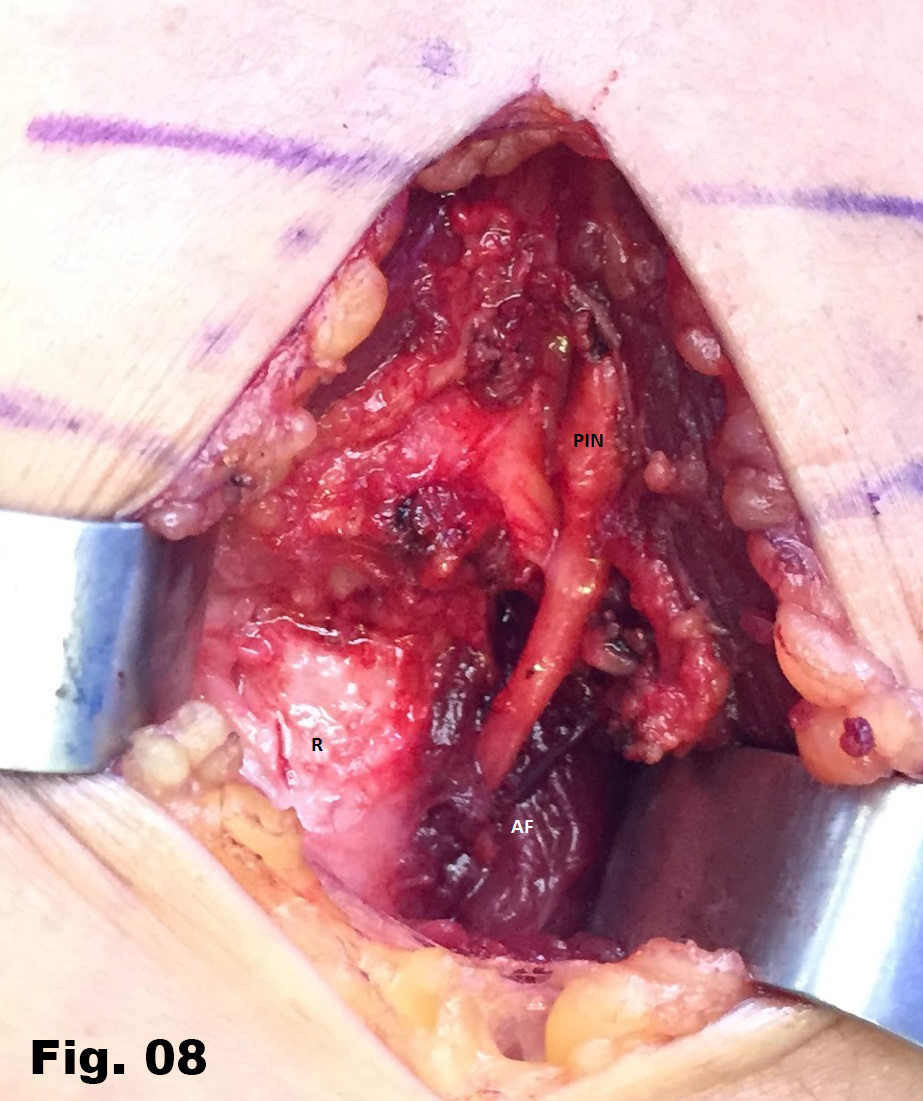

A 51-years-old healthy female, with no history of upper limb injuries, complained of an anterior and proximal left forearm tenderness associated with weakness of the extensor muscles of the forearm. An ultrasound scan was performed and demonstrated a thickened and hypoechoic posterior interosseous nerve (PIN) at the arcade of Frohse, with hypervascularization of the perineurium. In its deeper aspect, there was a subtle irregularity of the radial metaphysis (Fig1,2). The plain film showed a sessile irregularity of the anterior region of the metaphysis (Fig 3). Unenhanced MRI and CT scan were also performed. The CT scan showed the irregularity of the radius (Fig 4) and in the MRI (Fig 5), it was reported as an osteochondroma like metaphyseal lesion of the radius. Initial treatment included a corticosteroid injection around the PIN, but without decrease of symptomatology. The orthopedic surgeon then proceeded with an osteochondroma resection to release the PIN. The upper limb surgical team performed the surgery (Fig 6), and they found a thickened, hyperaemic PIN, adjacent to the osteochondroma (Fig 6,7). They resected the osteochondroma and debrided the PIN (Fig 8). The patient recovered full muscular strength and the tenderness progressively disappeared.

Fig 8: Radius (R) after resection of the osteochondroma. The radial recurrent artery is identified next to the PIN at the arcade of Frohse,.